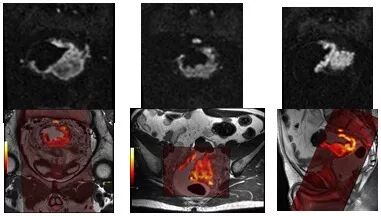

▲ 前列腺癌患者成像对比

与传统 DWI 成像相比,Pioneer 的高清 DWI 大幅度提高了图像的空间分辨率,降低了失真程度,病灶的位置和范围的显示准确程度得到了显著的提升,最右侧与常规解剖图像的融合精准吻合。

▲ FOCUS 技术对于直肠癌的显示也达到了极高的标准